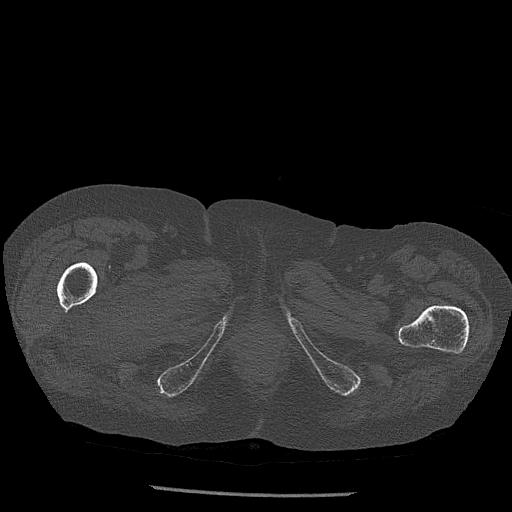

91569 3/25 両股正面とラウエン 70歳女性 人工骨頭+バンクーバー